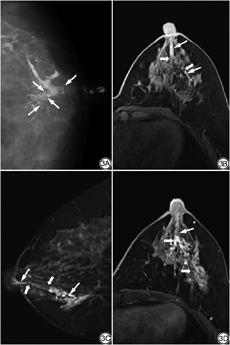

45例48个患乳GL的影像表现如下:(1)导管扩张40个,多发生在主导管,其次为二级导管,少见三、四级导管,表现为不同程度、不均匀性增宽;(2)导管僵直呈枯树枝状13个;(3)导管边缘毛糙、模糊8个;(4)导管破坏4个(1个为乳头状瘤伴硬化性腺病,3个为DCIS伴微浸润);(5)导管扭曲5个;(6)导管细小2个(1个末端局部稍增宽,然后狭窄呈鼠尾状,为乳腺增生,另一个导管细小,但有中断,为IDC);(7)正常1个(导管乳头状增生);(8)对比剂进入间质2个(1个为导管乳头状瘤,另1个呈潭湖征,为IDC);(9)有1个显示导管外有一肿块,该导管呈受压征象,术后该肿块为导管乳头状瘤,说明该肿瘤发生在另一支导管内;(10)充盈缺损33个;(11)多发结节状囊状充盈区7个,有4个于囊内见充盈缺损;(12)导管中断20个,其中在导管中断处和该导管支配区域见多发微钙化2个(均为恶性病变,图1),中断区见肿块2个(1个为恶性,1个为导管乳头状瘤伴重度不典型增生)。

45例48个患乳MRI表现如下:(1)导管显示43个,可扩张或不扩张,表现为自乳头向后的管状影,T1WI及T2WI可为高、低、等信号,信号高低与溢液性质有关,往往T1WI及T2WI信号相反,有4个信号相同,于T1WI及T2WI均呈高信号,其中2个为血性溢液,应与出血距检查时间的长短有关;7个恶性病变均见管状异常信号,这些管状信号往往与导管分布一致,可是连续的、间断的或突然中断(图1);(2)肿块样强化(22个,有2个为囊实性病变,肿块最大为31 mm×42 mm×24 mm,为囊实性肿块,病理为导管乳头状瘤)、灶点强化(7个)、非肿块样强化(7个)、导管样强化(9个)、环状或串环状强化(4个),这些强化灶可是单一的、多发的或混合的强化,多在病变导管支配范围内或中断处;未见强化(6个);(3)对41个病变测量了ADC(有6个因未见强化灶和1个强化灶小而无法测量),16个<1.150×10-3 mm2/s(其中包括5个恶性病变);(4)EER:15个<80%,26个>80%,7个恶性病变3个<80%,4个>80%(同样有6个因病变未见强化和1个病灶小无法测量);(5)TIC:Ⅰ型23个、Ⅱ型6个、Ⅲ型13个,未见强化6个(分别为导管乳头状瘤1个、乳腺增生伴囊肿1个、导管上皮乳头状增生1个、乳腺增生3个),7个恶性病变Ⅰ型1个、Ⅱ型4个、Ⅲ型2个;(6)MIP图显示血运增加13个,正常35个,7个恶性病变血运增加6个,正常1个。

MRI对乳腺癌的检查有较高的敏感度,对可疑钙化恶性病变的阳性预测值及准确度均高于乳腺X线检查,其敏感度及阴性预测值达100.00%[24],但乳腺MRI在评估PND中的作用仍然存在争议。本研究结果与文献[25, 26, 27]一致,MRI对识别导管病变有较高的敏感度及特异度,对识别乳腺癌的敏感度明显高于GL,两者均有很高的特异度与高阴性预测值,有助于排除恶性肿瘤。虽然本组病例GL与MRI检查在敏感度、特异度、阳性预测值、阴性预测值、准确度之间的差异没有统计学意义(P>0.05),但BERGER等[14]学者的统计是GL和MRI在敏感度和特异度方面存在显著差异,敏感度分别为69.00%和92.00%,特异度分别为39.00%和76.00%,并且MRI在检测PND患者的任何类型病变方面具有更高的诊断性能,这可能与本研究病例数较少或入组病例的具体情况有关。尽管如此,本组MRI对PND的特异度明显大于GL,说明MRI对恶性病变的评估优于GL。本研究有1个病例GL显示中断的导管区域发现肿块,被评价为BI-RADS 5类,而MRI从肿块形态、强化方式、DWI及血液动力学方面的表现也评价为BI-RADS 5类,但病理结果是良性病变,提示影像学对一些病例良、恶性病变的区分确实存在困难,不过值得注意的是,该病例伴有重度不典型增生,从超微结构来看,这种不典型增生病例细胞的某些形态特征已具有潜在的恶性趋势[20];所以,对于GL,发现导管中断区域见微钙化或肿块是诊断恶性病变较为可靠的征象;没有这些特定的征象,尽管表现导管中断和破坏,对良、恶性病变的鉴别也存在一定的困难,本研究有1个导管乳头状瘤伴硬化性腺病显示导管破坏。

BERGER等[14]、BOISSERIE-LACROIX等[28]认为对于有乳头溢液而乳腺X线摄影及超声检查正常的患者,MRI在识别需要切除的病变方面有很好的性能,MRI正常建议随访是安全的,可避免不必要的导管切除。MRI不需要导管插管,有助于提高患者的舒适度;不仅能观察导管内情况,还可以评估邻近组织、皮肤及淋巴结,多序列、多参数成像及动态增强给良、恶性病变的鉴别提供了更多的信息,在评估乳腺癌侵袭乳头乳晕复合体方面具有高敏感度(90.00%~100.00%)[29]。本研究MRI术前对乳腺癌评价为BI-RADS 5类明显高于GL(6∶3),而且两侧乳房同时成像,有利于与对侧乳房进行比较,本组有1例患者因左侧乳头溢液,MRI不仅观察到左乳的病变,且同时发现右乳有一肿块,病理结果为导管乳头状瘤伴DCIS,因该侧乳腺无乳头溢液而没有纳入本研究病例统计,如果只做GL,右乳病变将会漏诊。MRI对发现导管扩张的能力也与GL相当,本研究两种检查方法发现导管扩张分别为43个和40个,MRI可因导管内液体的性质不同,于T1WI及T2WI显示不同的信号,往往2个序列的信号相反或信号相同,而本组7个恶性病变均显示了这种异常信号的导管扩张。当然,本研究病例MRI是晚于GL所做,GL的图像解读会给MRI的判断提供参考,两种检查均未在同一天进行,GL所使用的对比剂不会给MRI信号造成影响,本研究注意到,GL显示充盈缺损的区域,MRI往往发现肿块样强化。